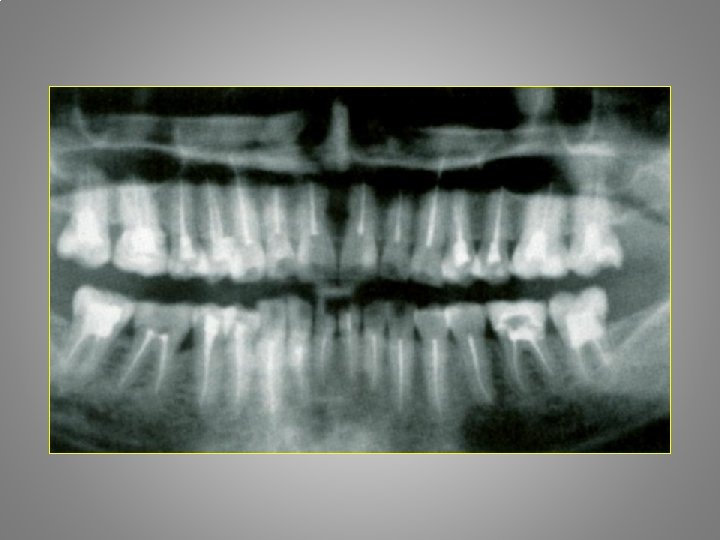

Types of orofacial pain Odontalgia : - Exposed dentin - Caries - Pulpitis - Apical periodontitis - Craced tooth sy. - Occlusal trauma - Periodontal abscessacute necrotising gingivitis - Periodontitis